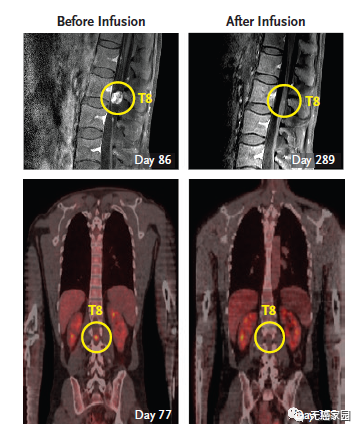

脑室内注射CAR-T细胞,首次消灭实体瘤

2016年12月,NEJM曾报道过1例利用CAR-T技术治疗脑胶质瘤的案例。一名50岁的男性,确诊为高级别脑胶质瘤,先后做了手术、放疗、替莫唑胺化疗等常规治疗,6个月后疾病复发。这时他参加了一项临床试验,接受靶向IL13Rα2的CAR-T治疗。不过这个疗法,有些“惊悚”。

主管医生通过核磁共振检查发现:这位病友脑部有5个病灶;因此,先通过手术切掉其中的三个大的,还剩下两个较小的由于位置深,无法切除。主管医生就给他的病灶处直接插了一个管子,然后通过这个管子,把CAR-T细胞打了进去,分3个批次,进行了多次的细胞回输。最终,肿瘤完全消失,疗效维持了8个月左右。

第二轮CAR-T疗法结束后,Richard Grady脊索内肿瘤出现剧烈萎缩